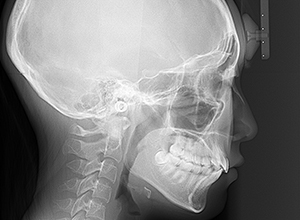

| X-Ray所見 | |

| セファロ所見 | 下顎頭はやや後方に位置しているが骨体部、下顎枝共に大きく上部構造体に対してバランスよく位置付いていた。中顔面は奥行きがあり下顔面高の高さは高くなかった。 |